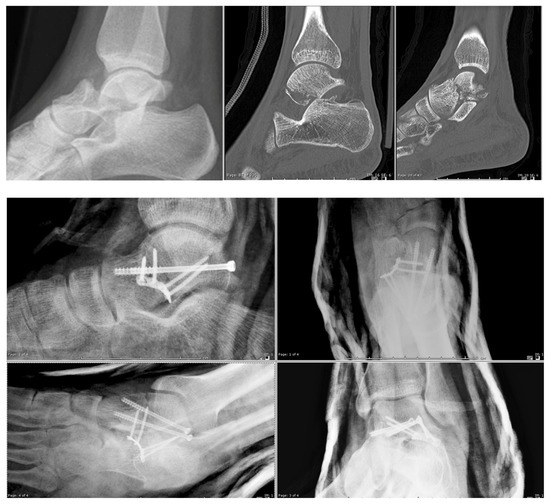

2. Materials and Methods

2.1. Surgical Technique

3. Results